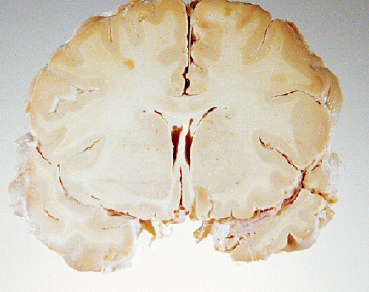

在这项新研究中,伦敦大学学院的神经病学家约翰·科林奇(John Collinge)及同事对8名在36~51岁间死于克雅病的患者进行了尸检。这些患者都曾在接受生长激素治疗(后来发现他们使用的生长激素被朊蛋白污染了)后感染了克雅病。而真正令人惊奇的是,研究人员发现,虽然研究对象中有6名患者年龄尚轻,不应出现阿尔茨海默病的症状,但他们的脑内都存在成块的β-淀粉样蛋白,而这正是阿尔茨海默病的典型病征。